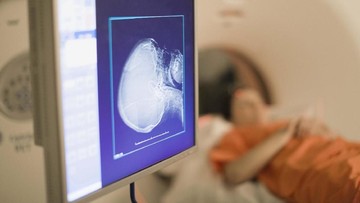

Seorang wanita berusia 22 tahun terluka parah saat menjalani tes magnetic resonance imaging (MRI). Hal ini disebabkan penggunaan mainan seks pada bagian anus.

Pasien dikatakan menggunakan mainan seks '100 persen silikon' pada saat pemeriksaan. Namun benda ini memiliki inti logam yang mampu merespon gaya magnet tersebut.

Sejauh ini, belum ada detail jelas terkait hal tersebut. Namun menurut laporan petugas kesehatan, pasien tersebut berteriak setelah dilakukan MRI dan langsung dibawa ke rumah sakit.

Dari hasil pemeriksaan, terlihat adanya benda asing berupa sex toy. Benda tersebut ditarik dari anus ke dalam rongga dada, yang sepanjang perjalanannya dapat merusak organ dan jaringan.